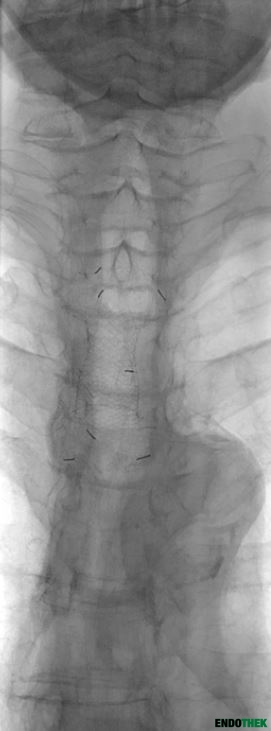

St.p. abdomino-rechtsthorakale Ösophagusresektion mit Magenschlauchinterponat bei langstreckiger, narbiger, hochgradig rezidivierender Ösophagusstenose im distalen und mittleren Drittel